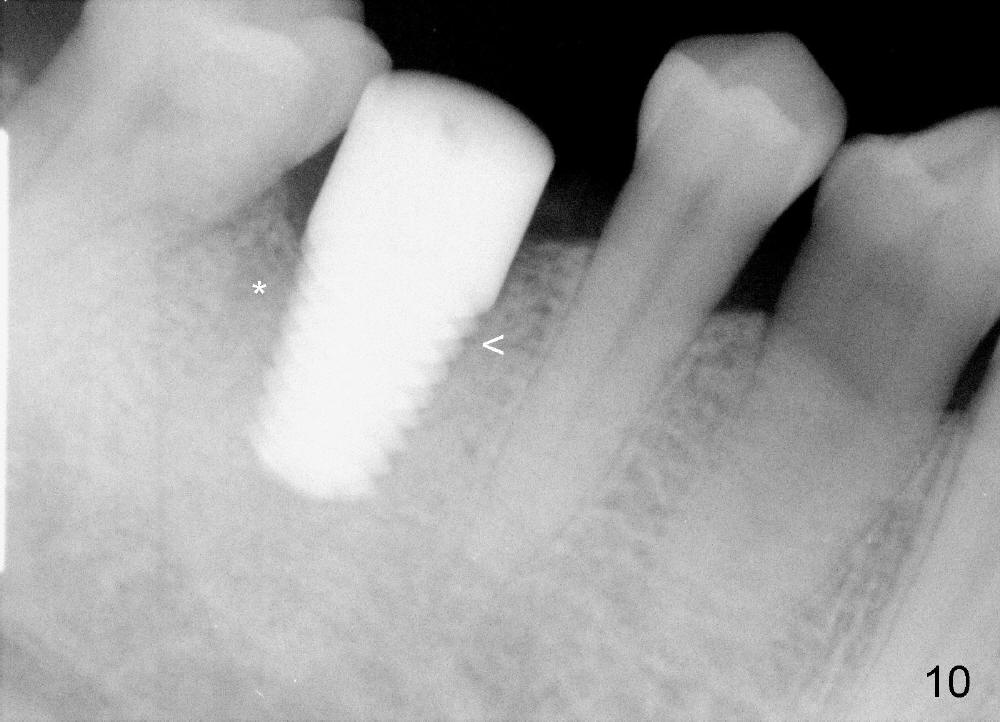

The distal socket is closed completely with suture, whereas the mesiobuccal space is partially closed with collagen gauze and suture (Fig.8 *). The wound is then covered by perio dressing. The gingiva heals around the implant 18 days postop (Fig.9). Three months postop, the implant is stable. The mesial upper portion of the threads appears to have better contact with the bone (Fig.10 <, as compared to Fig.7); the density of the distal socket seems to increase (*). There is no buccal plate atrophy (Fig.11 ^). Supragingival margin is designed for the crown to prevent periimplantitis (Fig.12)